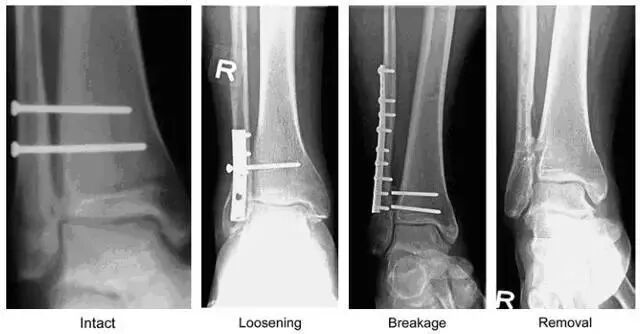

图 1  下胫腓联合螺钉示意图

由左向右分别为完整、松动、断裂、取除后的下胫腓联合螺钉(图片来自文献 [1])